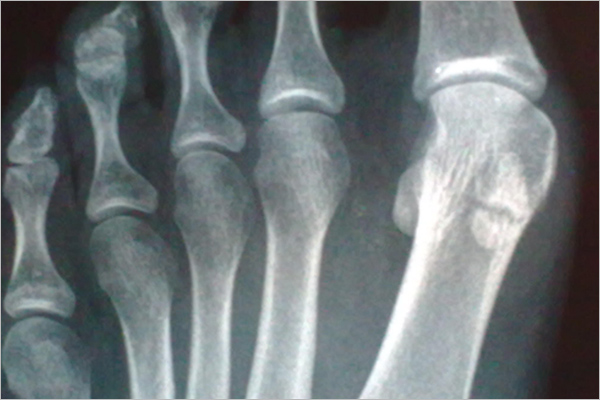

¿Qué huesos forman el miembro inferior?

El miembro inferior, al igual que el miembro superior, también está dividido en tres segmentos principales: el muslo, la pierna y el pie. Cada uno de estos segmentos contiene huesos…